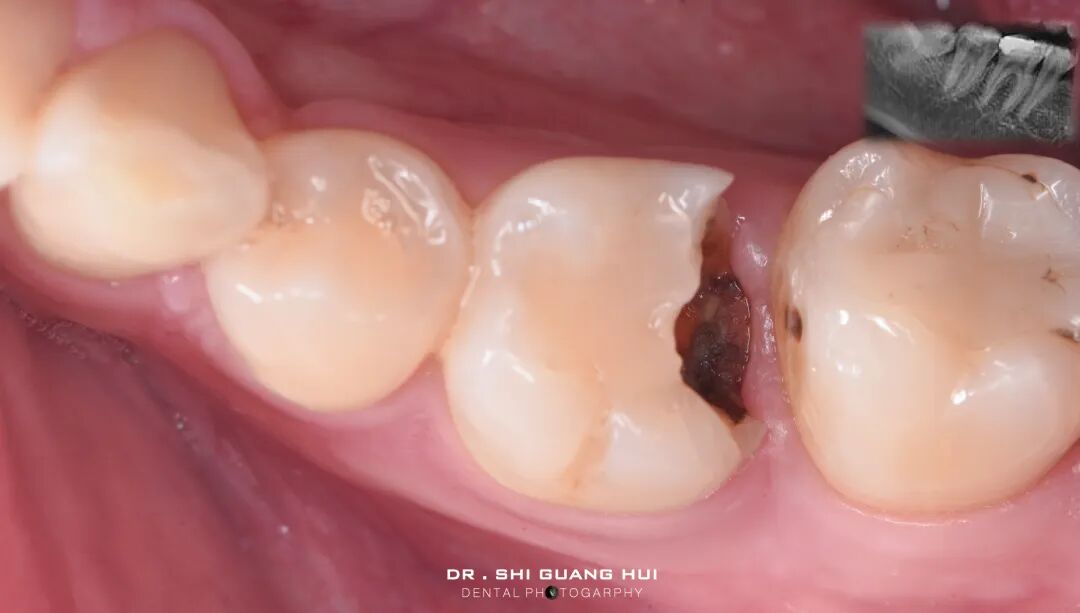

修复体制作完成,检查边缘密合性,邻面接触。

氢氟酸处理修复体,超声震荡后,涂布硅烷偶联剂静置。

橡皮障隔离四个单位,清洁,抛光牙面。

试戴修复体,检查修复体就位情况,边缘密合性。

试戴颊侧观

27微米氧化铝进行牙面喷砂

颊侧观,可见粘接面平坦。

进行磷酸酸蚀。

舌侧观

树脂水门汀粘接,去除多余粘接材料

各个面光固化60秒。

粘接后即刻

粘接后颊侧观,可见边缘密合。

邻面接触尚可

进行牙面抛光。

粘接后口内即刻。

咬合检测

口内颊侧观

术前术后对比